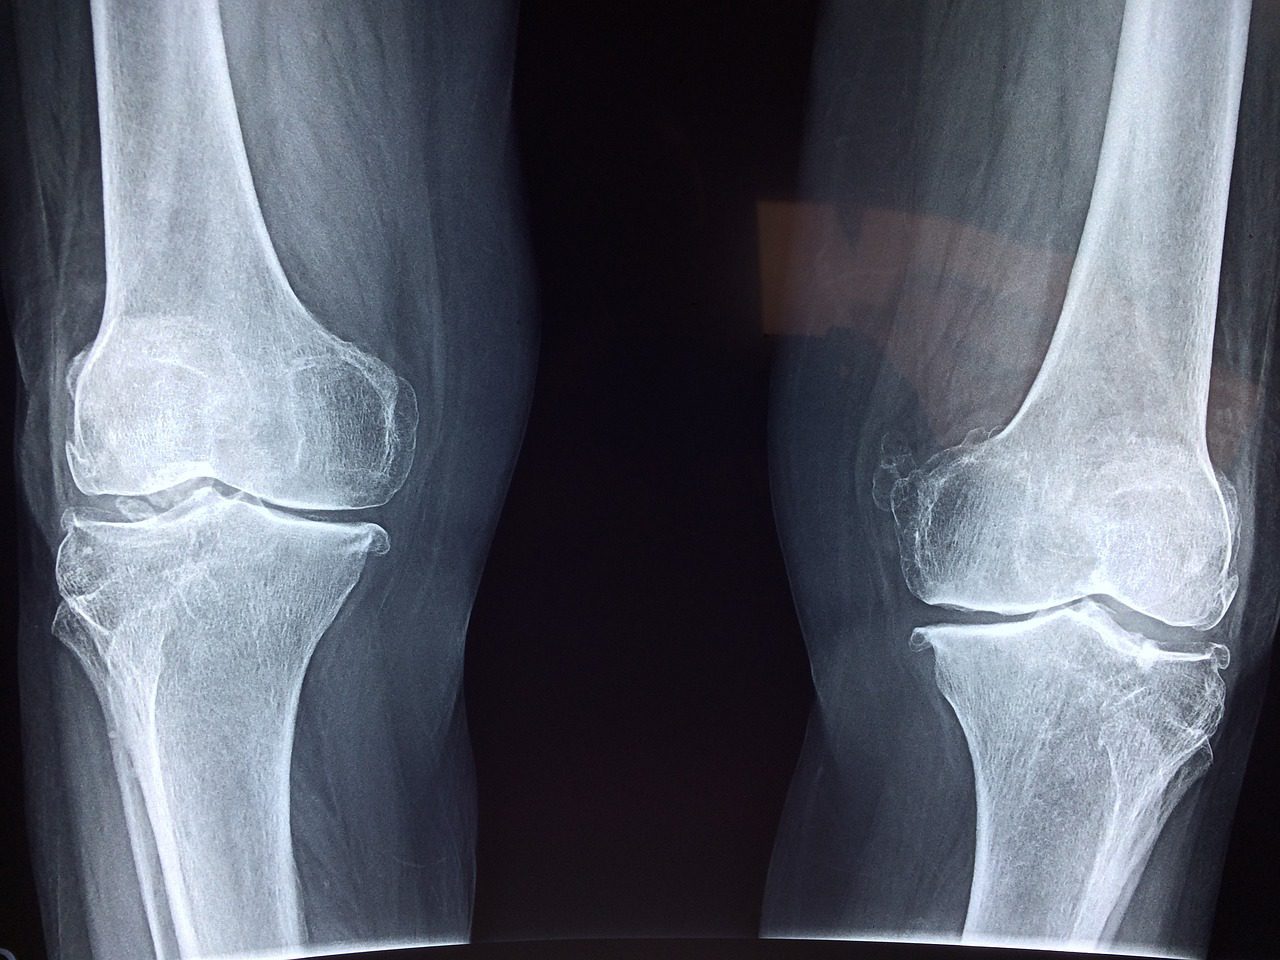

根據國民健康署2017到2020年「國民營養健康狀況變遷調查」,65歲以上長輩大約每7人就有1人骨質疏鬆。潘立昕說明,骨質疏鬆風險因子包括體重過輕、重度抽菸或飲酒、服用可能造成骨質疏鬆藥物,或罹患容易骨質疏鬆疾病,如糖尿病、甲狀腺亢進等。

潘立昕建議,若家中有65歲以上女性長輩、70歲以上男性長輩,或是具有骨質疏鬆風險因子者,包括即將停經或停經後女性長輩、年齡介於50至70歲男性長輩,都應儘早檢查骨質密度。

潘立昕以1名75歲女性門診病患為例說明,個案在浴室不慎滑倒,跌斷右側髖關節,住院開刀後檢查左側髖部,骨密度已達骨質疏鬆程度,患者才驚覺本身有骨質疏鬆問題。

經醫師仔細詢問,發現這名病患自45歲就停經,每天至少抽一包菸、喝一杯250c.c.高粱酒,且菸齡高達40年以上,具多重骨質疏鬆風險因子,好在病患手術後傷口癒合穩定,迅速改善生活方式及接受骨鬆治療,並厲行戒菸戒酒,後續未再發生骨折情形,生活穩定健康。

潘立昕也特別提醒,若曾有骨鬆性骨折病史,應及早接受骨質疏鬆檢查及治療,以預防再次骨折;骨質疏鬆屬於骨骼代謝相關問題,建議快帶長輩到內分泌及新陳代謝科門診諮詢、就診。(編輯:陳政偉)1130906